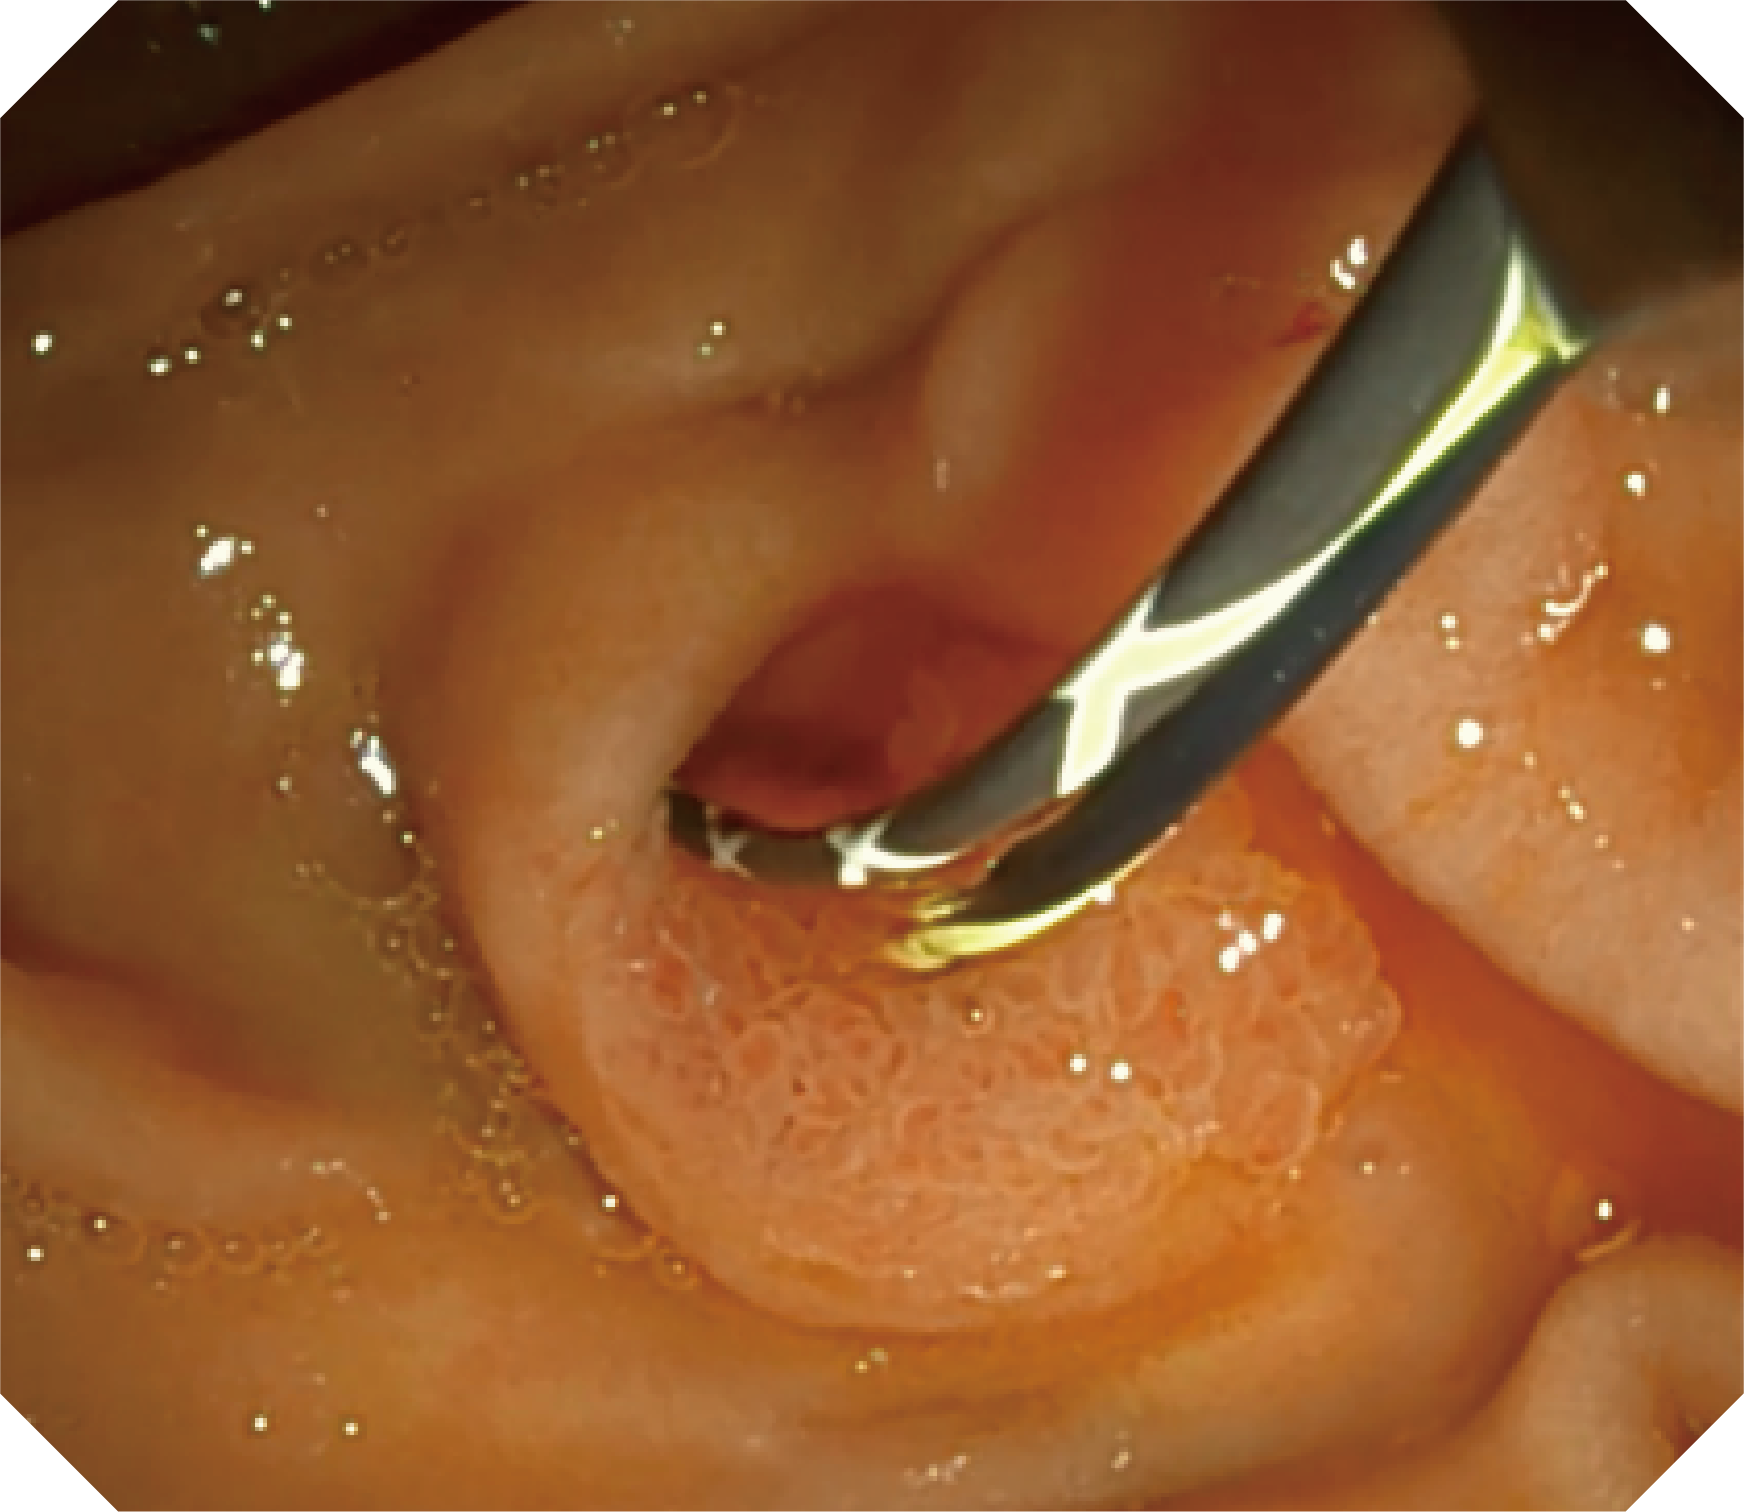

4.2mm大钳道,器械交换更顺畅

优异的手术器械抬举性

当切开刀伸出视野外时,导向面引导其回归视野